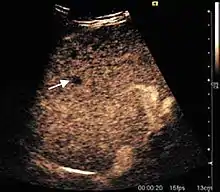

Hepatocellular carcinoma (HCC)

It is the most common liver malignancy. It develops secondary to cirrhosis therefore, ultrasound examination every 6 months combined with alpha fetoprotein (AFP) determination is an effective method for early detection and treatment monitoring for this type of tumor . Clinically, HCC overlaps with advanced liver cirrhosis (long evolution, repeated vascular and parenchymal decompensation, sometimes bleeding due to variceal leakage) in addition to accelerated weight loss in the recent past and lack of appetite.

HCC appearance on 2D ultrasound is that of a solid tumor, with imprecise delineation, with heterogeneous structure, uni- or multilocular (encephaloid form). An "infiltrative" type is also described which is difficult to discriminate from liver nodular reconstruction in cirrhosis. Typically HCC invades liver vessels, primarily the portal veins but also the hepatic veins . Doppler examination detects a high speed arterial flow and low impedance index (correlated with described changes in tumor angiogenesis). The spatial distribution of the vessels is irregular, disordered. CEUS examination shows hyperenhancement of the lesion during the arterial phase. During the portal venous phase there is a specific "wash out" of ultrasound contrast agent (UCA) and the tumor appears hypoechoic during the late phase. Poorly differentiated tumors may have a stronger wash out leading to an isoechoic appearance to the liver parenchyma during portal venous phase. This appearance was found in approx. 30% of cases. The described changes have diagnostic value in liver nodules larger than 2 cm.